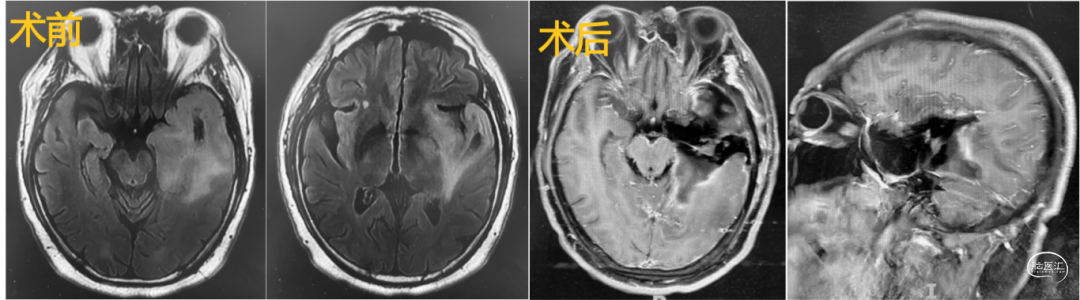

1.基底节-丘脑-颞叶内侧肿瘤切除术